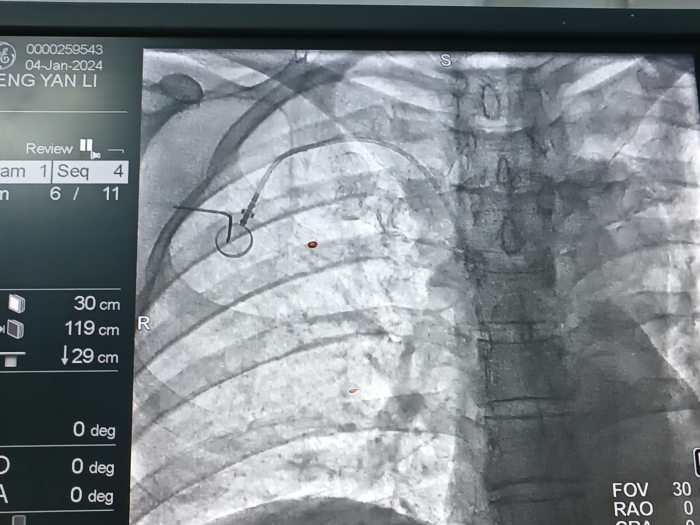

为患者开展超声引导下经腋静脉穿刺输液港植入术

输液港植入术后定位图

结合患者情况,王亚鹏博士与肿瘤科医生团队对患者术前评估及穿刺路径进行了详细讨论。经过综合考虑,团队决定采取穿刺点远离锁骨、不易导致夹闭综合征的经腋静脉通路植入输液港。手术仅用时20分钟,患者术后一周拆线,目前恢复良好。